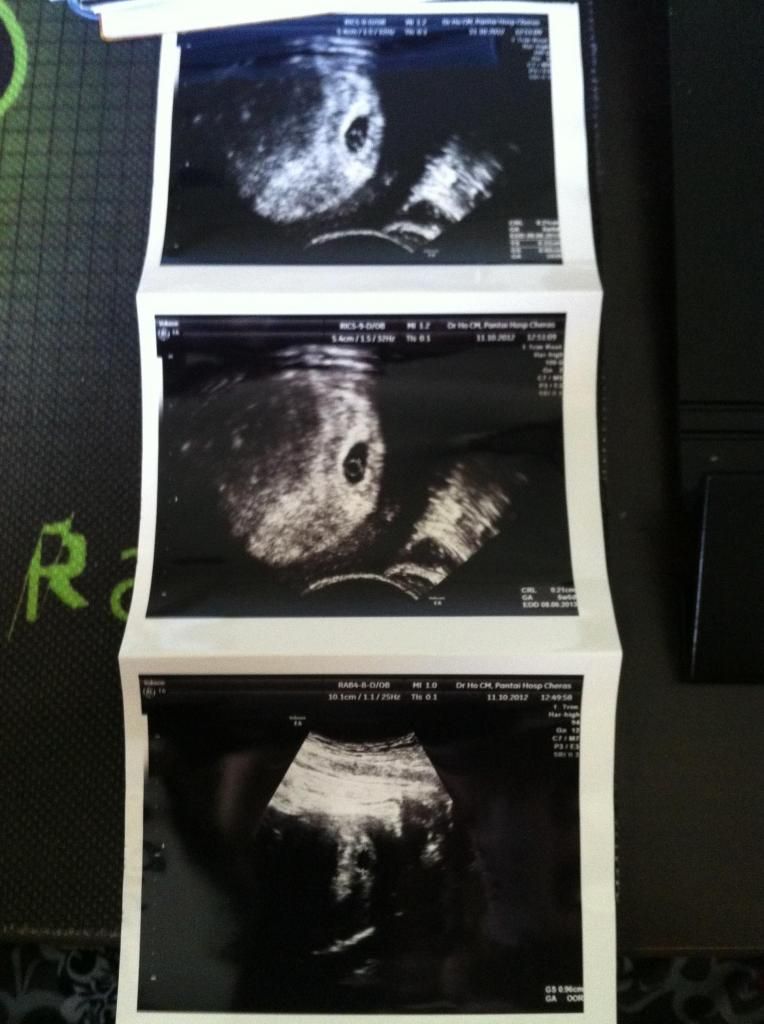

产检终于可以看到bb了。。

一如往常,dr tan永远是高朋满座。。每次都等上1-2个半小时。。这次等2个小时。。

可是看bb才15分钟。。。

bb现在1.5kg,刚刚好的重量。。